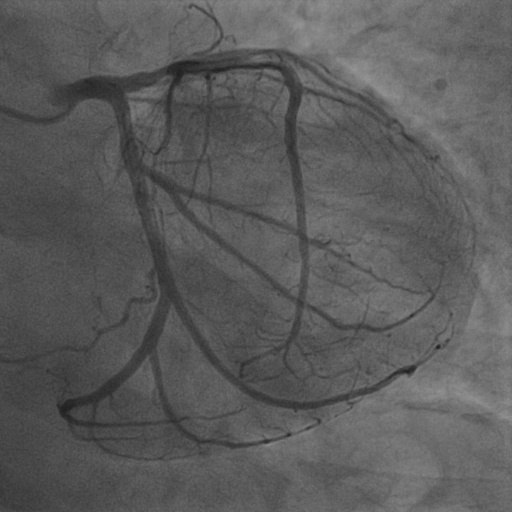

4.1 XACV Dataset

We collect 111 complete records of coronary artery X-ray videos, encompassing the injection, flow through the blood vessels around the heart, and dissipation of the contrast agent. Subsequently, we establish the XACV (X-ray Angiography Coronary Video) dataset. Each video consists of varying numbers of high-resolution coronary artery X-ray images. We invite experienced radiologists to annotate the vascular regions, focusing on one or two frames where the contrast agent is most prominent in each video. The XCAD dataset contains only a single image, and the CADICA video dataset does not provide corresponding ground truth. Therefore, in the following experiments, we conduct all the analyses on our collected XACV dataset and the corresponding GT for each sequence. In Figure 5, we show that compared to other publicly available datasets, XCAD [33] and CADICA [19], our dataset exhibits finer annotations in the vascular regions, providing an advantage for future related tasks. The development and use of our dataset have been approved by our institution’s IRB.